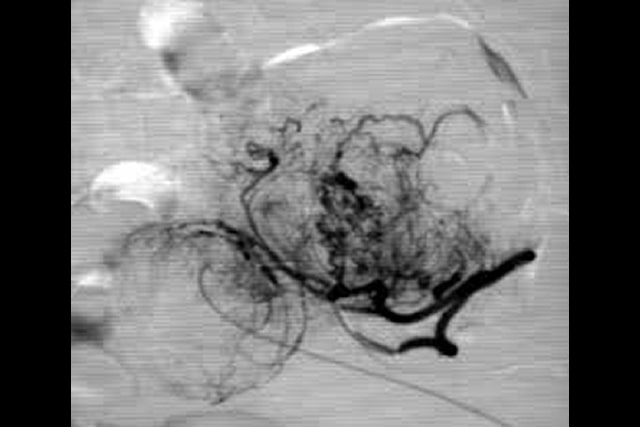

Uterine Artery Embolization is a safe technique, introduced by Ravina in 1995, then endorsed by world agencies (NICE, FDA...). It is painful in the first week after the procedure and has a risk of permanent amenorrhea (loss of periods) of 3% in patients in those under 40 years of age and 15% in those over 40 years of age.

It is not considered the first choice in patients who wish to become pregnant at some point in their life.